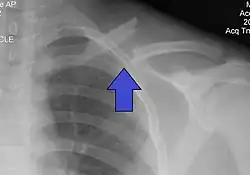

| X-ray of a left clavicle fracture | |

The basic method to check for a clavicle fracture is by an X-ray of the clavicle to determine the fracture type and extent of injury. In former times, X-rays were taken of both clavicle bones for comparison purposes. Due to the curved shape in a tilted plane X-rays are typically oriented with ~15° upwards facing tilt from the front. In more severe cases, a computerized tomography (CT) or magnetic resonance imaging (MRI) scan is taken. However, the standard method of diagnosis through ultrasound imaging performed in the emergency room may be equally accurate in children.[6]